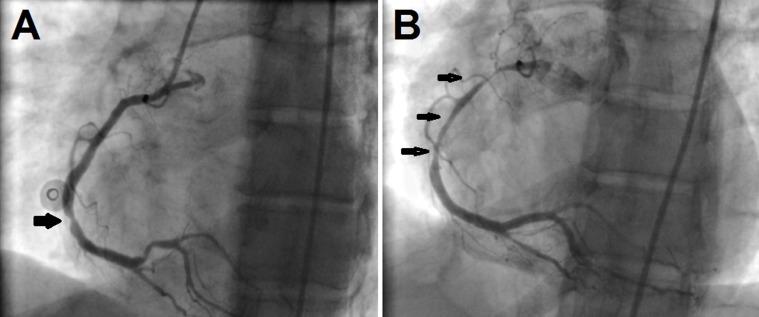

We describe a 52-year-old woman with no significant cardiovascular risk factors who experienced several episodes of spontaneous and coincident multivessel coronary artery spasm, which led to myocardial infarction as well as malignant arrhythmias. Coronary angiography revealed severe migratory narrowing in the left anterior descending artery and right coronary artery.

我们描述了一名52岁女性,无明显心血管危险因素,经历了数次自发性和同时发生的多支冠状动脉痉挛发作,导致心肌梗死以及恶性心律失常。冠状动脉造影显示左前降支和右冠状动脉严重的游走性狭窄。